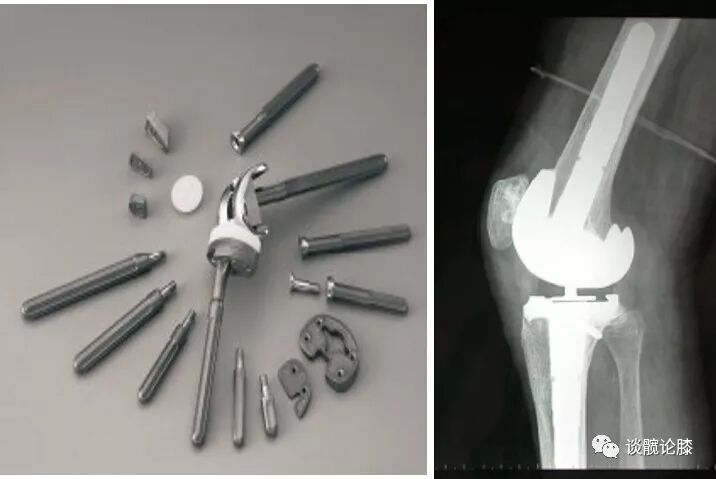

TKA术中软组织的平衡情况直接影响到术后膝关节的稳定性及功能的改善。充分良好的软组织平衡有助于减少假体松动、磨损、提高TKA的疗效。

4、选择合适的假体